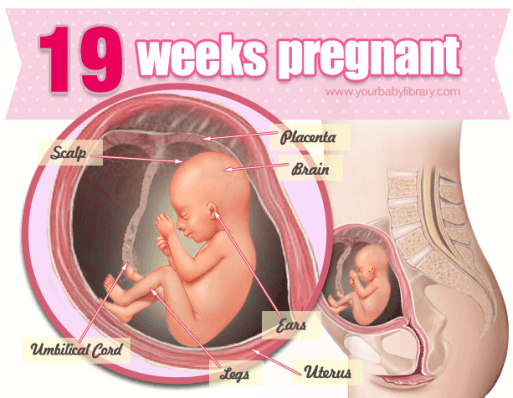

در هفته نوزدهم بارداری کودک شما به اندازه یک انبه است و شما در میانه ماه پنجم حاملگی خود به سر میبرید. پوششی به نام ورنیکس، سطح پوست جنین را احاطه میکند. این پوشش سفید و چرب، جنبه محافظتی دارد. سلولهای عصبی و حواس پنجگانه کودک در حال رشد و تکامل است. قد او 22.8 سانتیمتر و وزنش 272 گرم میباشد. از این زمان به بعد، شما کاملاً متوجه حرکات جنین خواهید شد. متورم شدن پاها، کمر درد و احساس درد در شکم، از علائم مادر طی این هفته است. اگر در انتظار سونوگرافی سه بعدی بودید، وقتش فرا رسیده است!

کودک شما در حال ایجاد یک پوشش سفید به نام vernix caseosa بر روی پوست خود است. این پوشش چرب و سفید است و ممکن است شما مقداری از آن را در زمان زایمان و به دنیا آمدن نوزاد خود ببینید. این پوشش چرب کمک می کند تا نوزاد در هنگام تولد، راحت تر از کانال تولد عبور کند. همچنین او را در برابر مایع آمنیوتیک کیسه آب محافظت می کند. جلوگیری از عفونت، تنظیم دمای بدن و مرطوب نگه داشتن پوست بدن کودک، از دیگر عملکردهای بسیار مهم vernix caseosa است.

حواس پنجگانه کودک شما در حال تکامل است. برای این منظور، سلولهای عصبی او برای تکامل حس بویایی، چشایی، شنوایی و بینایی در مغز، رشد و نمو می کند.

افزایش چربی از دیگر رخدادهای هفته 19 حاملگی است. چربی هایی به نام چربیهای قهوهای به بدن جنین اضافه می شود. نوزادان پس از ترک رحم به این چربی ها برای گرم نگه داشتن بدن نیاز دارند.